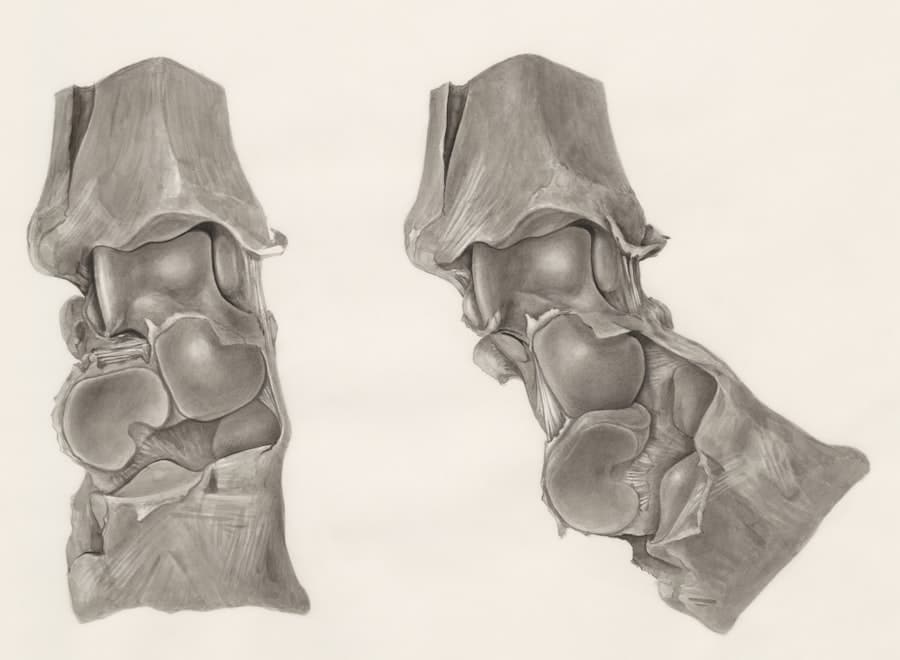

A surgeon with extensive experience, a strong reputation, and a history of successful outcomes will generally command higher fees. This isn’t necessarily a negative; it often reflects a higher level of skill and a deeper understanding of facial anatomy and aesthetic principles. For rhinoplasty, which is known for its meticulous nature, choosing a board-certified facial plastic surgeon or a plastic surgeon with specific expertise in rhinoplasty is paramount.